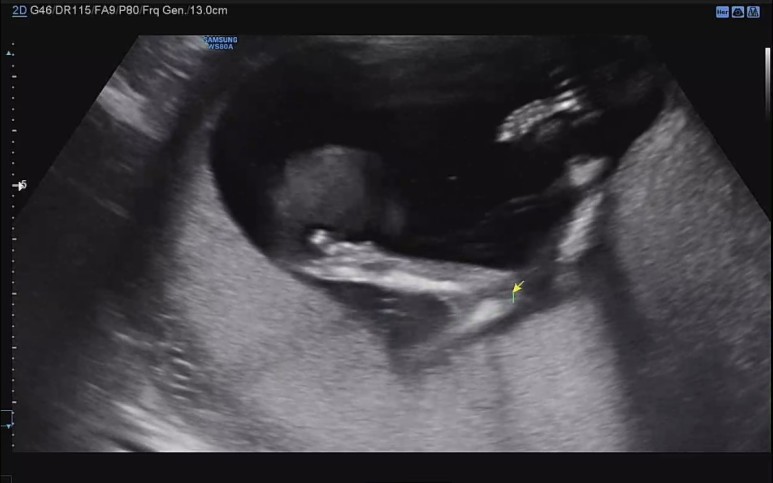

콧대도 확인하고.

벌써 머리통이랑 콧날이 예쁜것 같아 내새꾸.

초음파 선생님이 엉덩이 사이를 열심히 들여다 보셨지만, 탯줄이 교묘하게 가리고 있어서 도저히 성별을 가늠할 수 없다고 하셨다. 그런데 내 느낌엔 슬쩍 슬쩍 지나가는 화면에 다리 사이에 아무것도 보이지 않는게 자꾸 포착되어서 딸인것 같은 느낌적인 느낌을 느꼈다..!